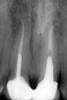

Л Ю С Я Опубликовано 25 марта, 2013 Поделиться Опубликовано 25 марта, 2013 (изменено) Сегодня собрала несколько СИЦ на работе и сделала Р-снимке:оказались все рентгеноконтрастны! Глассин-рест http://ib3.keep4u.ru/s/2013/03/25/25/2508bb9211e3063f4e91446de2d5357f.jpg Фуджи http://ib3.keep4u.ru/s/2013/03/25/60/6001b44958dd590cabe8d7e9e7968656.jpg Витремер http://ib2.keep4u.ru/s/2013/03/25/c8/c84b2541635d866bcf442cca8fa7cede.jpg аквамерон http://ib2.keep4u.ru/s/2013/03/25/b5/b5a316946eb494d7c63aa6ed9bef6964.jpg Изменено 25 марта, 2013 пользователем Л Ю С Я Ссылка на комментарий

Ico Опубликовано 25 марта, 2013 Поделиться Опубликовано 25 марта, 2013 Сегодня собрала несколько СИЦ на работе и сделала Р-снимке:оказались все рентгеноконтрастны! Глассин-рест http://ib3.keep4u.ru/s/2013/03/25/25/2508bb9211e3063f4e91446de2d5357f.jpg Фуджи http://ib3.keep4u.ru/s/2013/03/25/60/6001b44958dd590cabe8d7e9e7968656.jpg Витремер http://ib2.keep4u.ru/s/2013/03/25/c8/c84b2541635d866bcf442cca8fa7cede.jpg аквамерон http://ib2.keep4u.ru/s/2013/03/25/b5/b5a316946eb494d7c63aa6ed9bef6964.jpgЛюся.Если вы их в канал в нужном объеме заведете,выставите экспозицию в 0.8 - 0.12,то посмотрите.Я ж не с потолка так утверждаю.Кетак,Кормакс,Фуджи 1 и для преэндо еще используют "Блокаут". Ссылка на комментарий

Л Ю С Я Опубликовано 25 марта, 2013 Поделиться Опубликовано 25 марта, 2013 (изменено) Из интернета стырилВнимательно посмотрите: в 2.1 пора а в 1.1 нет. В моляре в дист ОК в мед нет. Я не думаю что в моляре в разных каналах разный сиц и поэтому рентгеноконтрастность неодинаковая Изменено 25 марта, 2013 пользователем Л Ю С Я Ссылка на комментарий